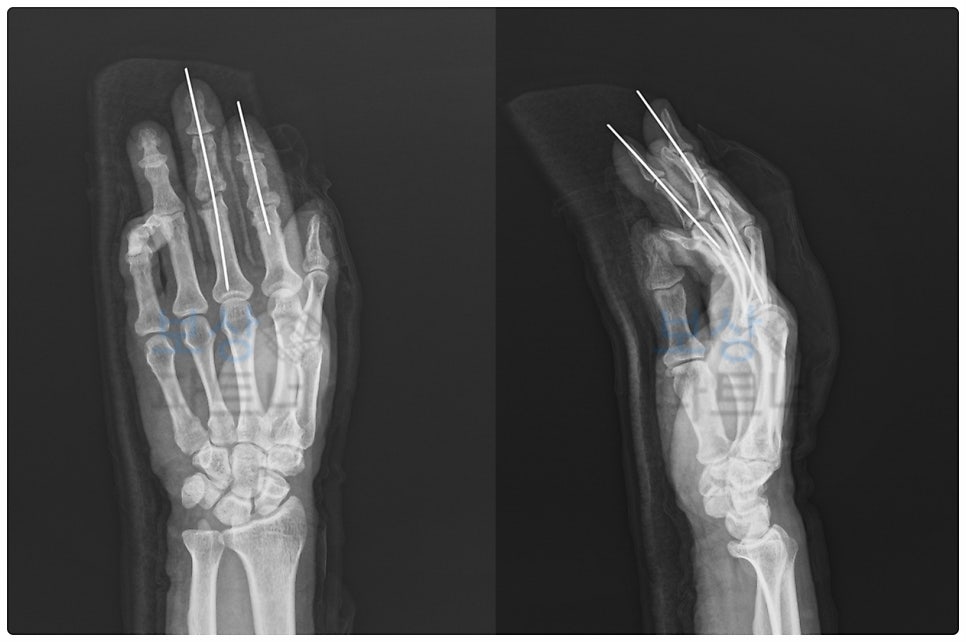

이 사고로 엄지, 검지, 중지 세 손가락에 걸쳐서 절단, 골절, 힘줄 파열이 발생하였는데요. 엄지의 절단된 부위를 덮기 위해 **피부조직 이식 및 재건술(국소 피판술)**이 이루어졌습니다.

그리고 검지와 중지는 골절 부위를 절개하여 직접 눈으로 보고 뼈를 정렬한 뒤, 금속 핀으로 뼈가 정상 위치에 유합되도록 도와주는 핀고정술을 진행하였습니다. 이러한 과정은 고난도 수술로서, 꼭 수지 전문 병원에서 시행할 필요가 있습니다.

세 군데의 보험사에 후유장해 진단서, 의무 기록지 등 각종 서류를 제출하였고, 그 뒤로 약 두 달간의 분쟁이 있었습니다. 치열한 과정이 있었지만 결국 힘줄 파열, 부분 절단, 골절 부위 기능장애를 인정받았으며 상당한 금액의 보험금을 수령할 수 있었습니다.

엄지손가락뼈 일부 상실 (10%) 2수지, 3수지 뚜렷한 장해 (5% + 5% = 10%) 최종 장해지급률 (20%)